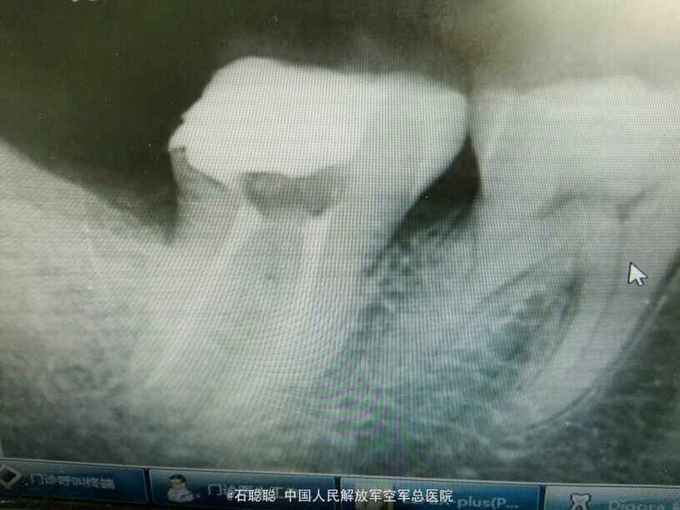

检查:右下7远中合面银汞充填体,边缘发黑,探针可探入,探痛+,冷+,叩痛-,不松动,牙龈未见异常 根尖片:右下7远中冠方见高密度充填影像,下方密度减低,近髓

诊断:右下7牙髓炎 治疗计划:右下7RCT后冠修复 处置:右下7“利多卡因”局麻下开髓,揭顶,探及近颊、近舌、远中3和根管口,略疏通,见血性渗出,冲洗,干燥,置失活剂,氧化锌暂封 一周后复诊:去除右下7暂封,测工作长度,近舌=19mm,扩大至30#,近颊=远中=18mm,扩大至35#,冲洗,干燥根管及髓腔,置CP棉球,氧化锌暂封 一周后复诊: 查:右下7叩痛-,不松动,氧化锌完整在位 处:去除右下7氧化锌暂封,试主尖,冷侧压充填,氧化锌暂封,建议一周后修复